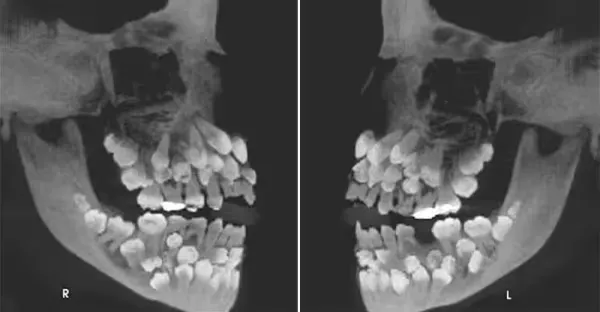

女童拔乳牙...X光驚見「81顆牙塞滿嘴」嚇壞牙醫:罕見

女童拔乳牙...X光驚見「81顆牙塞滿嘴」嚇壞牙醫:太罕見